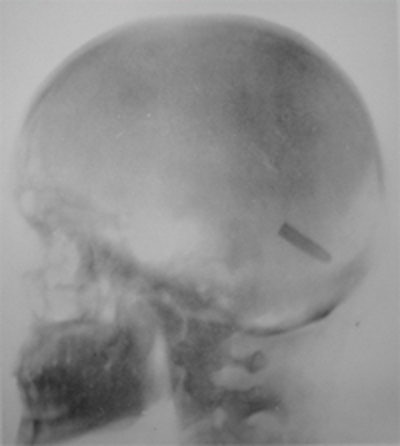

Private John Gretzer (left) received a bullet in his brain, which an x-ray detailed. Illustrated is a Mauser bullet in in the brain of John Gretzer (center) and the knee of Samuel Davis (right).